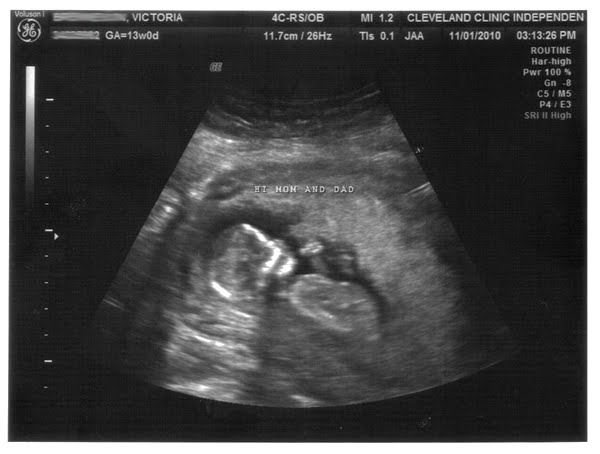

Here is the baby again. It now looks considerably more like a baby and less like a dinosaur, which I suppose is a good thing. I could also do without the cutesy text the ultrasound tech put on the image--I am not a cutesy person.

The good news here is that the NT measurement was 1.6 millimeters. The acceptable range is 2.2 millimeters to 3.something millimeters. My age alone (I guess I'm considered pretty young for this sort of thing) lowers the risk of chromosomal disorders significantly, to a factor of about 1 in 700. The results from the ultrasound and bloodwork (always with the bloodwork) skyrocketed those odds to 1/9000 for Down's Syndrome and 1/10000 for Trisomy 18. Those are good odds--I'll take them.